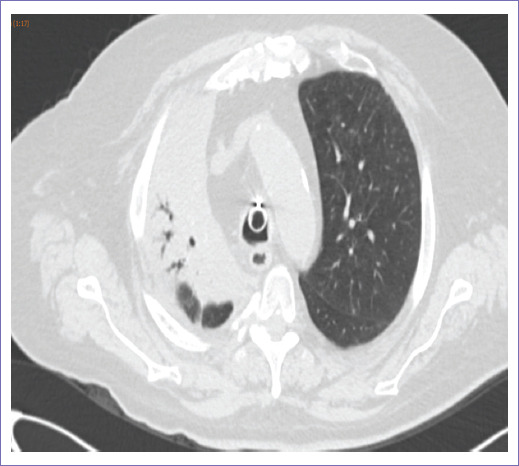

En el seguimiento posterior a dos meses valorado por el Servicio de Neumología, con sintomatología respiratoria a base de tos con expectoración blanquecina, se clasifica al paciente con neumonitis post-RT grado 2 (Fig. 3), por lo que se decide tratamiento con esteroide sistémico y esteroide/broncodilatador de acción prolongada (LABA) inhalado para reducir sintomatología.

Figura 3 Área en vidrio despulido lóbulo inferior derecho, datos en relación con el proceso inflamatorio.